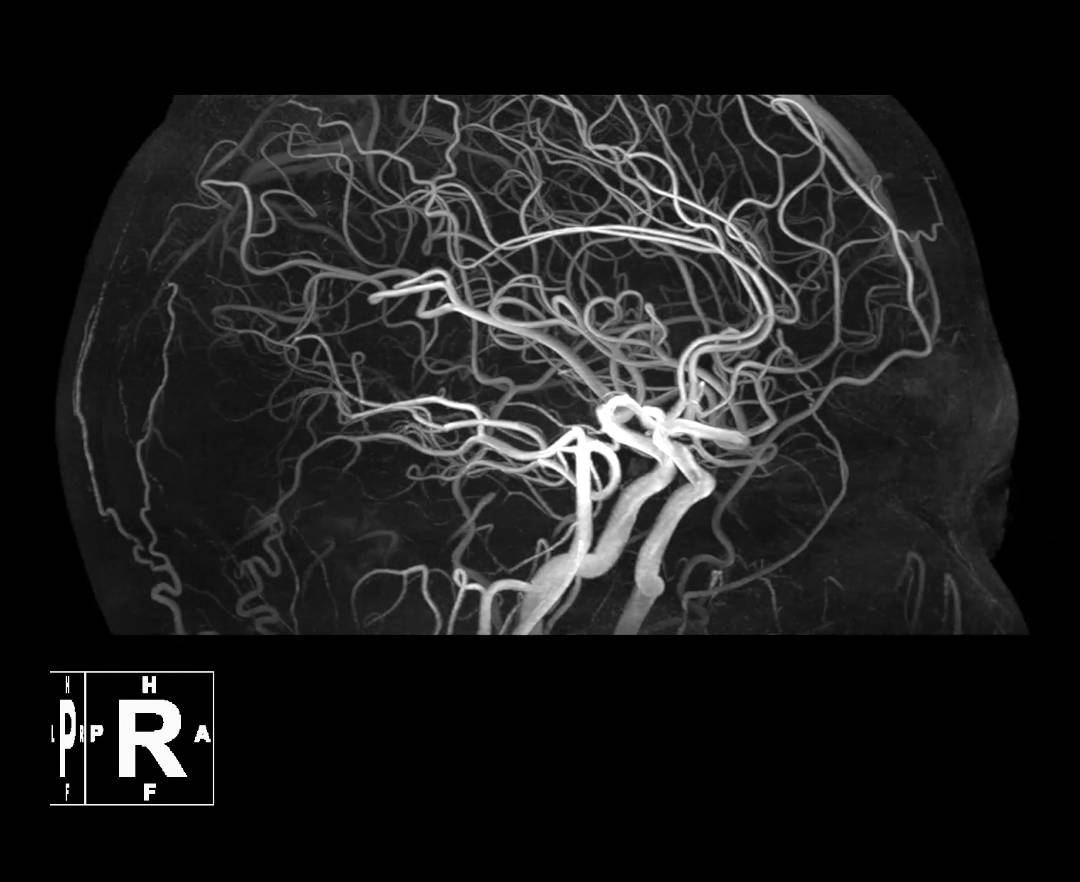

HEAD TOF

MRCA HRR*

MRCA*

*MRCA HRR & MRCA were Post-Processed by uOmnispace

1. UHF: Ultra-high Field. Here it means field strength ≥ 5T。Shi Z, Zhao X, Zhu S, et al. Time-of-Flight Intracranial MRA at 3 T versus 5 T versus 7 T: Visualization of Distal Small Cerebral Arteries. Radiology. 2022;305(3):E72. doi:10.1148/radiol.229027